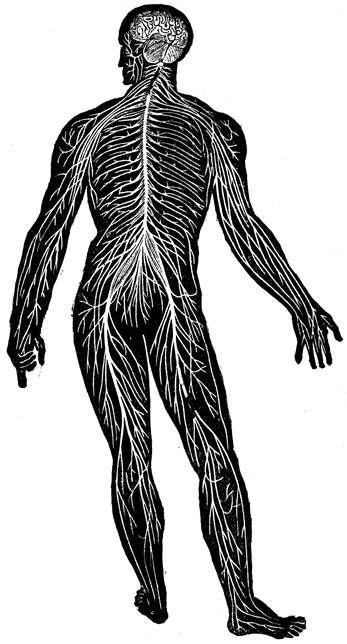

entire physical person by twelve pairs of cranial or cerebral nerves,

and by the spinal cord, which descends from the base of the brain

through a great foramen or opening midway between the ears, and

while passing down the spinal column gives off thirty pairs of

nerves.

The cranial nerves are all for the head, except the pneumogastric

or lung-stomach nerve, which belongs to the organs of respiration,

voice, and digestion; and the spinal nerves are all for the body,

except a few which ramify in the neck and in the scalp.

The entire nervous system is so instantaneously prompt in conveying

to the brain the impressions which originate feeling, and in conveying

from the brain the nervous energies that produce voluntary

motion and modify all the processes of life, that we feel as if we had

sensation and volition in every part of the body; or, in other words,

that our conscious existence was in the body; but we rationally

know that the sensation and volition occur in the brain, for neither

sensation nor voluntary motion can occur if the nervous connection

with the brain is interrupted by compression and section, or if the

brain itself be sufficiently compressed. When the brain is exposed

by an injury of the cranium, the pressure of a finger suspends all

consciousness and volition, making a blank in the life of the individual.

Animal life resides in the nervous system alone, and its character

is proportioned to the development thereof, of which the brain is the

principal mass. A subordinate portion of the general life, however,

is in the nervous system of the body, and in proportion as the brain

declines in development the relative amount of psychic energy in

the body is greater. Thus the body of the alligator after decapitation

is capable of sensation and voluntary acts, such as pushing

away an offending body with its foot. The character of the life in

the body is explained by physiology and sarcognomy. Its universal

presence is due to the universal diffusion of the nervous system,

of which the accompanying figure, showing the location of the spinal

cord and spinal nerves, will give a proper conception. In this figure

the spinal cord, with its thirty pairs of nerves, eight cervical at the

neck, twelve dorsal in the back, five lumbar in the loins, and five or

six in the sacrum (between the hips), is seen descending from the

base of the brain below the cerebellum (which is rather too large in

engraving), and proceeding throughout the body until lost in fine

ramifications which the microscope can scarcely trace, but which

quickly inform us if they are touched or disturbed.